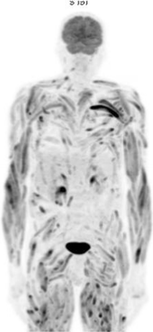

A 55-year-old man presented with a polydipsic syndrome and showed severe hypercalcemia. Medical history, laboratory tests and CT scan ruled out any malignant or iatrogenic cause. Granulomatosis was considered likely. There was no mediastinal lymphadenopathy and histology of the minor salivary glands was normal. A PET/CT scan showed strong 18F-FDG uptake in all skeletal muscles, suggesting myositis (Fig. 1). The CPK rate was normal. MRI of the legs showed a STIR-weighted hypersignal and a T1-weighted hypersignal of every muscle (Fig. 2). Muscle biopsy revealed an intramuscular non-necrotizing giant cell granuloma. Diffuse sarcoidosis myopathy was considered likely because of the absence of other granulomatous conditions. The evolution was rapidly favourable after glucocorticoid treatment. The patient completely recovered and a PET/CT scan showed a complete metabolic response (Fig. 3) at 3 months.